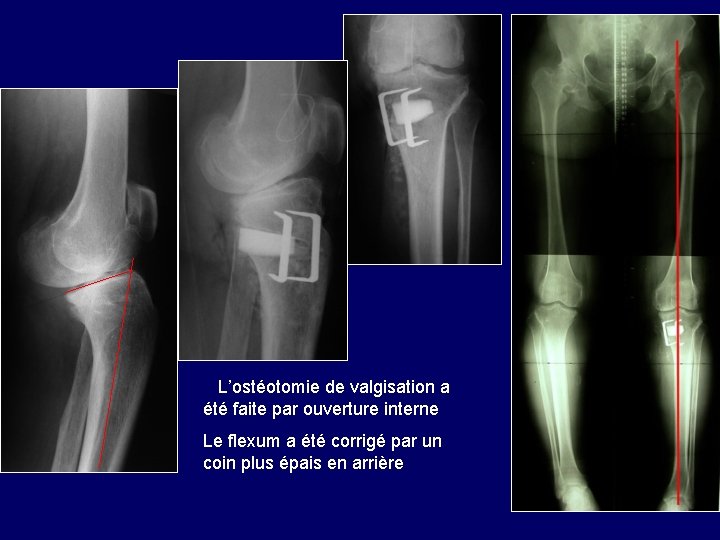

2/ Exemple de flexum Flexum majeur chez une femme présentant un polydystrophie avec atteinte des 2 hanches et arthrose du genou Le genu varum justifie une ostéotomie de valgisation On en profitera pour corriger aussi le flexum par une fermeture antérieure ou une ouverture postérieure

L’ostéotomie de valgisation a été faite par ouverture interne Le flexum a été corrigé par un coin plus épais en arrière